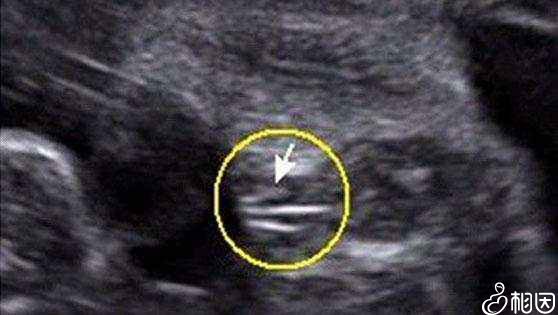

因为孕囊都是圆柱形的,每个B超师截取的时候截取得方位都会不一样。有的是横截取面,有的是竖截取面。所以只看图片是长的还是圆的是不能判断男女的。

孕囊看男女

通过孕囊数据看男女

打个比方,比如:40*20mm的孕囊,这样是根本没有办法判断的,表面看起来两个数据相差一倍,应该是男孩。但是错了,因为没有第三个数据。如果是40*40*20,那就肯定是男孩了。

但如果b超师截取横截面,孕囊就成了40*40的两个数据了,看上去就是圆的,结果造成了孕囊是圆的,但是生的是儿子。所以数据一定要三个,如果孕囊成等差比:40*30*20这样的就是女孩。